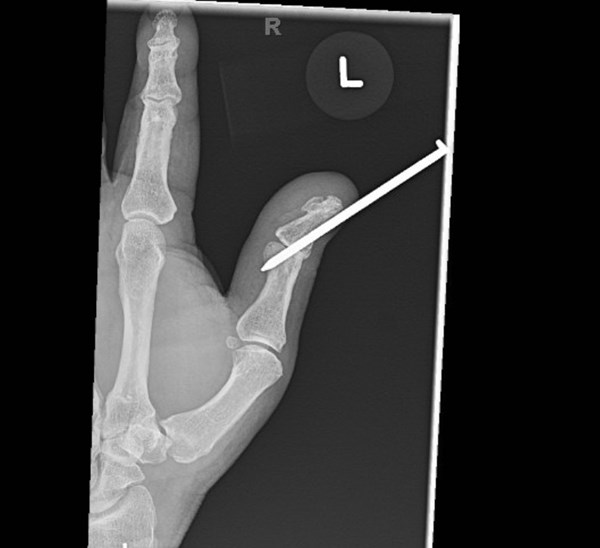

Radiographs were obtained including anterior-posterior and lateral views of the left thumb which demonstrated a penetrating injury of a metallic object (in this case, the threaded nail). The nail on X-ray did appear to pierce the base of the distal phalanx with extension through the interphalangeal joint into the thumb proximal phalanx with an associated vertically oriented split fracture of the proximal phalanx, evident with increased radiolucency on these films. No gas within the soft tissues or other identified foreign bodies; fractures, dislocation, or other acute bony abnormalities were noted. The hospital site has an orthopedic surgery residency program, and the orthopedic surgery resident was consulted given the bony involvement and the recommended outpatient management with an orthopedic hand surgeon.

Post-foreign body removal with cast application X-rays were obtained which redemonstrated the vertically oriented, longitudinal fracture of the left thumb proximal phalanx extending into the interphalangeal joint. Removal of the foreign metal nail also allowed for appreciation of an intra-articular fracture at the distal ulnar aspect of the proximal phalanx where the metallic nail had been previously located, and a distal phalanx base fracture as well. No retained metallic foreign bodies were identified. Of note, there was no involvement of the metacarpal phalangeal joint of the thumb, making this an isolated injury involving only a single joint of the thumb.